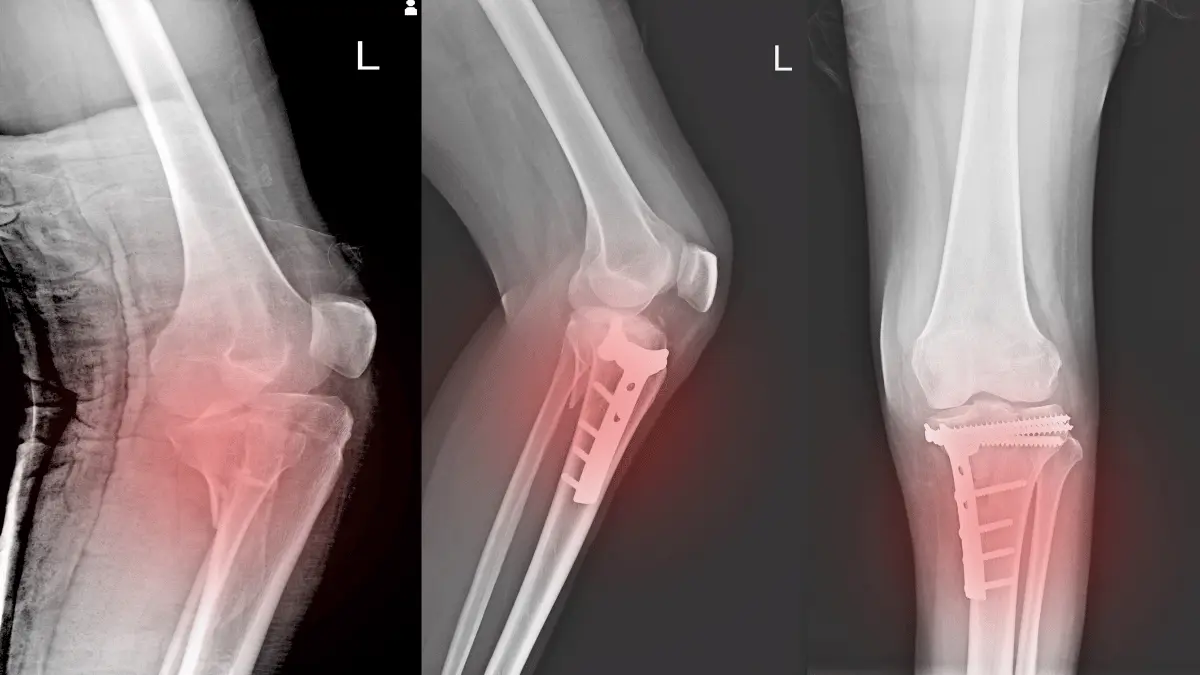

Cirurgia no fêmur é grave? Saiba os riscos e recuperaçãoA cirurgia no fêmur é considerada um procedimento de grande porte e requer cuidados especiais. Entender quando ela é necessária,… Leia mais »

Fratura de fêmur causa parada respiratória?A fratura de fêmur é uma das lesões ósseas mais graves, principalmente em idosos, e pode desencadear complicações sérias. Ao… Leia mais »

Por que idoso morre quando quebra o fêmur?A pergunta por que idoso morre quando quebra o fêmur é uma das questões mais frequentes que recebo em meu consultório. Como… Leia mais »

Cirurgia de fêmur em idoso é perigosa?Como ortopedista especialista em técnicas minimamente invasivas, muitos familiares chegam ao consultório querendo saber se cirurgia de fêmur em idoso… Leia mais »